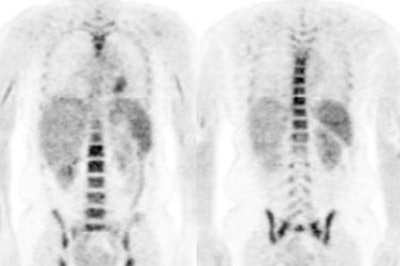

Metformin bowel activity: A large

amount of bowel activity can be seen in this patient

that was taking metformin. |

|